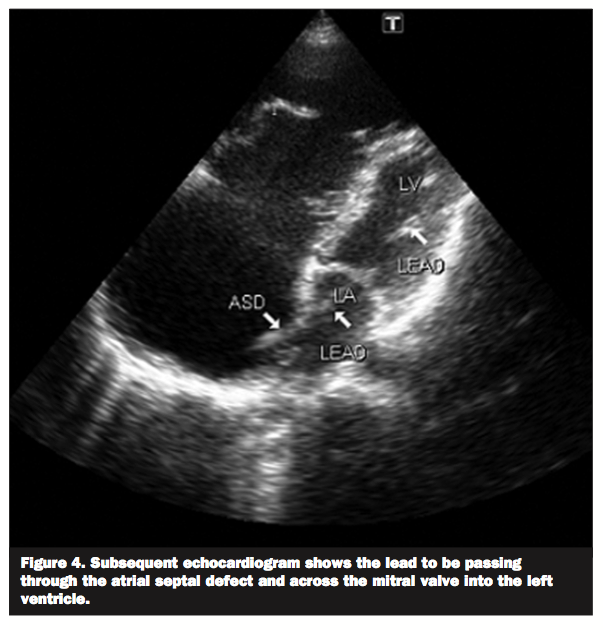

A 50-year-old male with congestive heart failure secondary to Ebstein’s anomaly presented for recurrent shocks from his implantable cardioverter-defibrillator (ICD). His electrocardiogram (ECG) (Figure 1) showed paced rhythm with right bundle branch block morphology which raised the question of left ventricular malposition of the ICD lead. On the postero-anterior chest radiograph (Figure 2) the tip of the lead was situated very far laterally to the left sternal border. A lateral chest

radiograph (Figure 3) showed the lead to be positioned posteriorly in the cardiac silhouette, which is consistent with left ventricular malposition. Subsequent echocardiography (Figure 4) showed the lead to be passing through the atrial septal defect and across the mitral valve into the left ventricle.

atrial or ventricular septal defects.1,2 It can cause thromboembolic events like stroke or peripheral arterial occlusion. This complication can be easily missed on intraoperative fluoroscopic imaging. ECG and chest radiographic findings often suggest the diagnosis. In proper positioning, the tip of the lead is expected to be adjacent to the left sternal border on the postero-anterior radiograph and to run anteriorly in the cardiac silhouette on the lateral radiograph. Definitive diagnosis can be established via echocardiography.